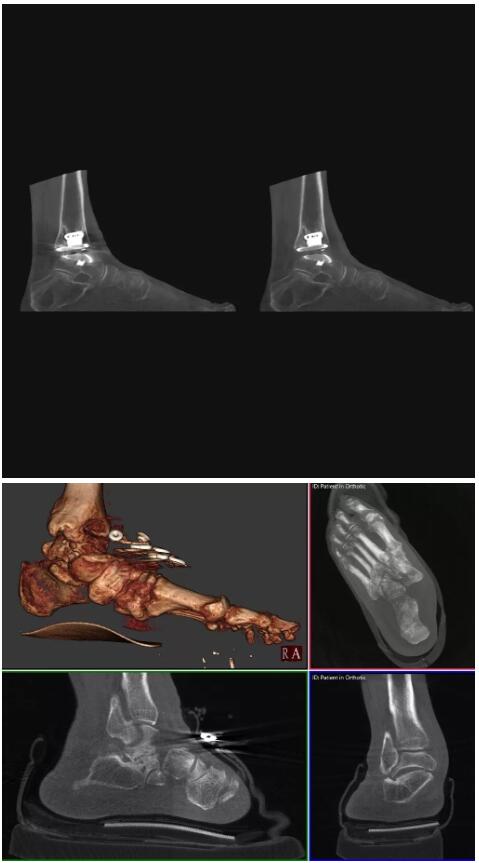

比如上面這款專用于足部和踝部掃查的CT成像系統(tǒng),患者在進(jìn)行CT掃查時(shí)只需要站在上面即可,雙腳站或者單腳站都可以,當(dāng)然,如果患者不是那么方便站著做完CT掃查,也可坐在上面。

這款CT掃查系統(tǒng)自帶屏蔽裝置,它的體積非常小,僅需要極小的空間即可,并不像常規(guī)CT那樣需要一間單獨(dú)的檢查室。此外,這種CT掃查的速度非常快,僅需30秒左右可以完成檢查,輻射劑量相對(duì)常規(guī)的CT要少許多,尤其適合醫(yī)院的骨科使用。

而患者站著做足部或者踝部做CT檢查還有個(gè)好處是,可以檢查患者在負(fù)重的情況下,骨關(guān)節(jié)的真實(shí)情況,而躺著做CT掃查時(shí)未必能看出來(lái)。負(fù)重CT掃查特別是對(duì)于受傷的運(yùn)動(dòng)員或者舞蹈員來(lái)說(shuō)意義更大,能夠更準(zhǔn)確地評(píng)估傷情,幫助他們盡早復(fù)原。

以上介紹的CT均來(lái)自國(guó)外同一家公司,這些CT均配置了可視化軟件,可以進(jìn)行切片、3D重建以及大型CT附帶的所有典型的操作功能。

以下是這些“特立獨(dú)行”的CT所拍出來(lái)的圖像: